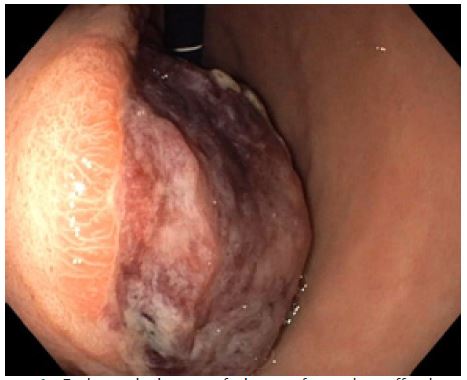

Subsequently, a staging CT scan with iodinated contrast medium confirmed the presence of the large stomach neoformation (9.5 cm in diameter) with an exophytic development (Figure 2). It was suspected to be a GIST and was in contact with the left hepatic lobe, the intra-abdominal wall, the pancreas, and the duodenum, without any lymphadenopathies or signs of possible metastasis (Figure 2).

After multidisciplinary discussion and a Gastrografin swallow to understand the patient’s GI anatomy (Figure 3), she underwent a partial gastrectomy, sparing the previous gastric-ileal bypass (Figures 4). The histological examination observed a low-risk GIST (Figure 5), CD117/c-Kit negative, with R0 margins and the mitotic count was 1 mitosis/5 mmq.

Figure 2: Contrast-enhanced abdomen Computed Tomography (CT) showing the stomach neoformation.

Figure 3: Images of the Gastrografin swallow ordered in time sequence.